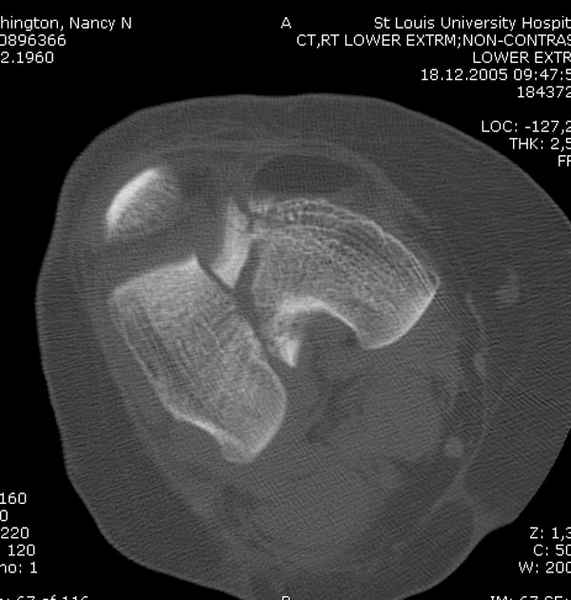

Приветствую всех коллег!!Во первых слева хотелось бы видеть четкую боковую проекцию а лучше КТ. По р-мам есть сомнения насчет повреждения суставной поверхности. При подобных переломах даже внутрисуставных без смещения хорошие результаты показал закрытый ретроградный остеосинтез универсальным бедренным стержнем Деост.Кстати при внутрисуставном переломе возможно применение вместо винтов стягивающих болтов!!(См. метод.Деост).При переломе справа также стержень Деост. Однако без открытия Вам не удастся устранить интерпозицию, только промучаетесь!Из минимального разреза удалите интерпозициб и фиксируйте стержнем. Причем универсальный стежень Деост позволяет фиксировать дистально минимум на трех уровнях!